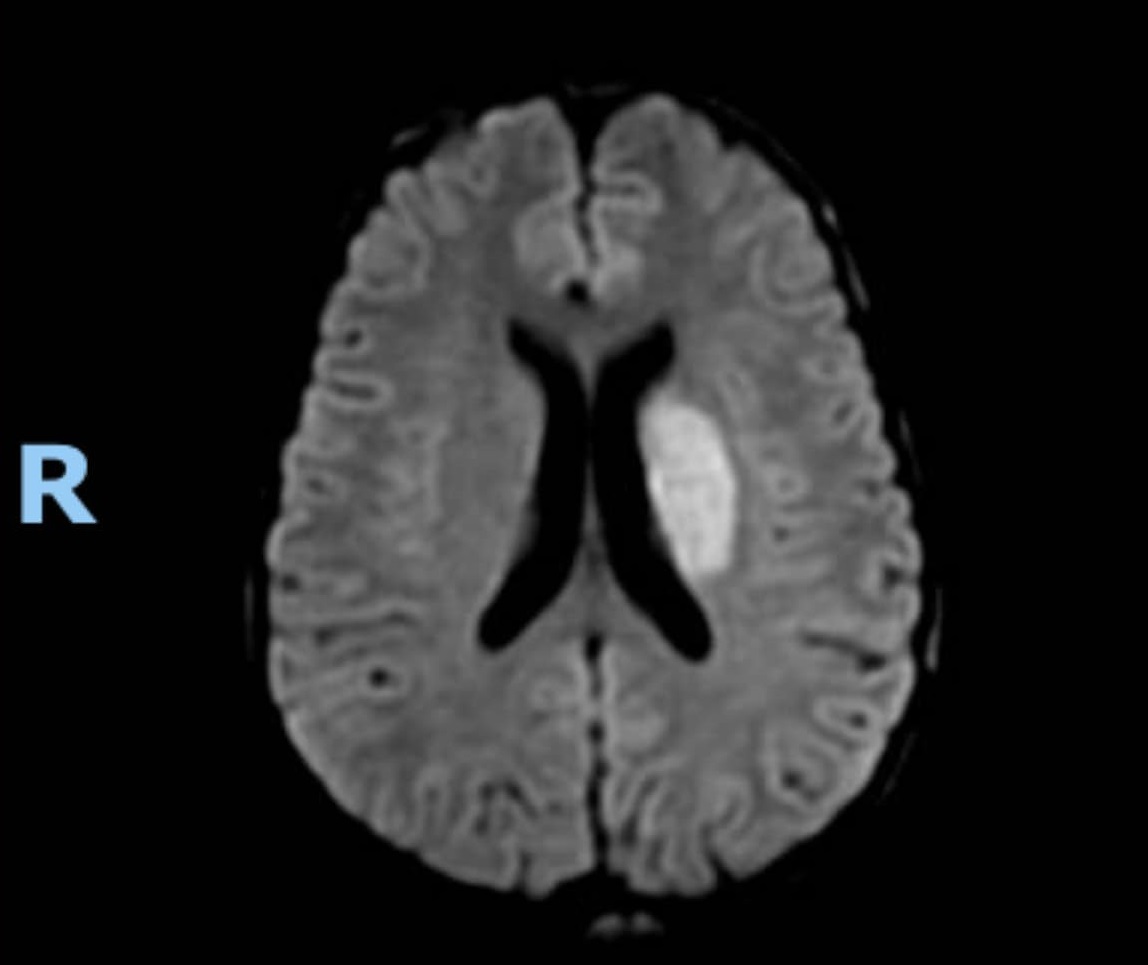

Mới đây, TS.BS Nguyễn Huy Thắng – Phó Chủ tịch Hội Đột quỵ Việt Nam, Chủ tịch Hội Đột quỵ TPHCM, Trưởng Khoa Bệnh lý mạch máu não Bệnh viện Nhân dân 115, chia sẻ trên trang cá nhân về một trường hợp bệnh nhân trẻ ngoài 20 tuổi, nhập viện trong tình trạng liệt nửa người phải. Bệnh nhân có tiền căn sử dụng thuốc gây nghiện. Khi nhập viện, các bác sĩ tiến hành chụp cộng hưởng từ não, cho hình ảnh nhồi máu não cấp vành tia T. Đây là bệnh nhân trẻ thứ hai gần đây, bị đột quỵ liên quan đến thuốc gây nghiện.

Chụp cộng hưởng từ não của bệnh nhân (ảnh: TS.BS Nguyễn Huy Thắng)